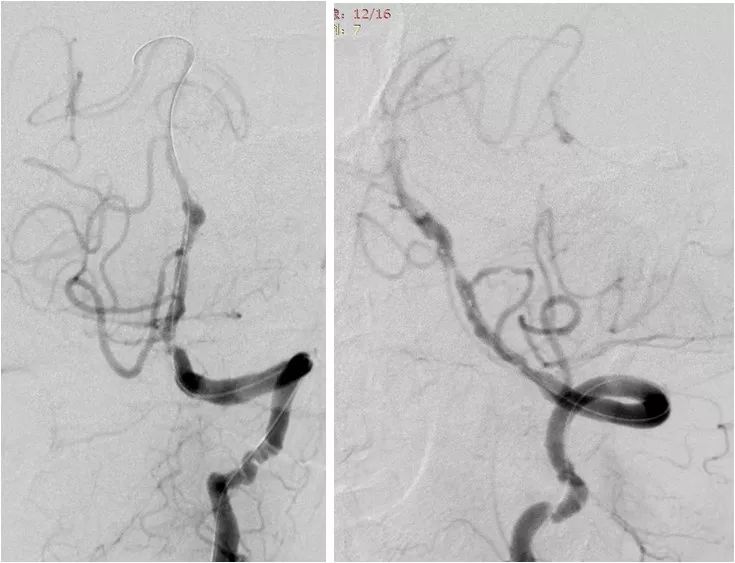

遂以大于命名压的压力后扩张支架。其后造影显示支架处无明显残余狭窄,支架近心端管壁侧后方见局部造影剂滞留,考虑血管夹层(红箭)(图10)。

图10

观察10余分钟后,造影复查无变化后结束治疗。

术后复查头颅CTA:支架内通畅(图12)。

图12

本例左椎动脉V4段重度狭窄,释放球囊扩张支架后即出现夹层,所幸夹层位于支架近心端逆血流方向,进一步撕裂可能性不大。椎动脉V4段狭窄,因合并钙化或者为纤维性斑块,在血管内介入治疗过程中常遇扩张困难。类似病变,如无充分扩张,放置任何类型支架,都会因支架贴壁欠佳,导致系统回撤困难,也易诱发急性亚急性血栓形成。此时选择稍小直径球囊或球囊扩张支架,有助于减少相关并发症。